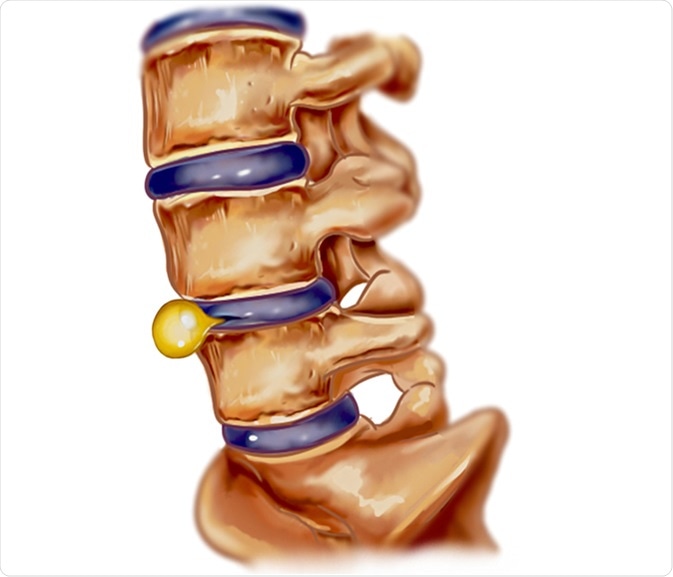

Slipped disc

Pelvic intervertebral disc prolapse or slipped disc is a condition in which the soft cushion of tissue present between adjacent spinal bones pushes out. A slipped disc can irritate nearby nerves, resulting in pain and numbness or weakness in an arm or leg. The pain worsens after sitting or standing, walking short distances, and with certain movements. The pain is more severe at night, and is accompanied by burning, tingling, and aching sensations on the affected area.

Slipped disc illustration. Image Credit: corbac40 / Shutterstock